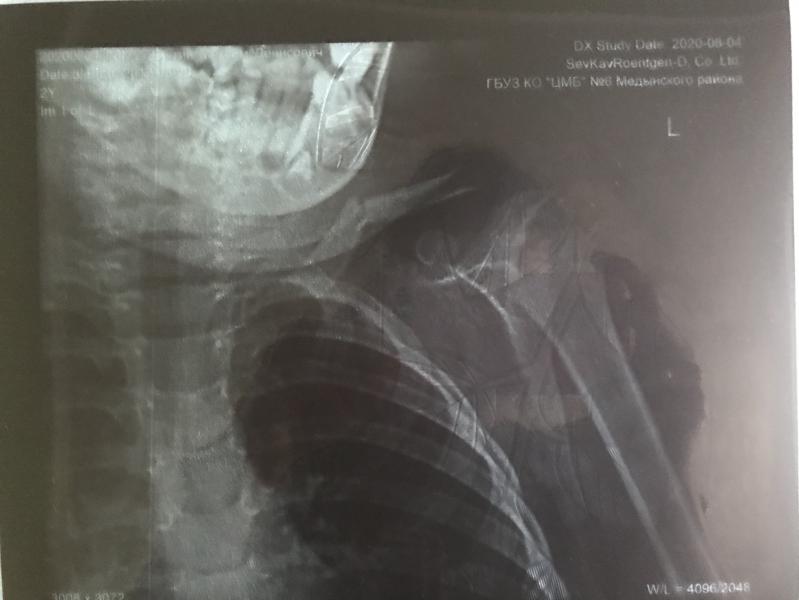

Упал с лестницы - перелом ключицы .....🤦🏽♀️ едем 🚘 в Калугу по направлению из ПК за консультацией ... Днюха в гипсе😥 хочу стереть 2020-й со всем что с нами произошло в этот год....😖

#переломключицы